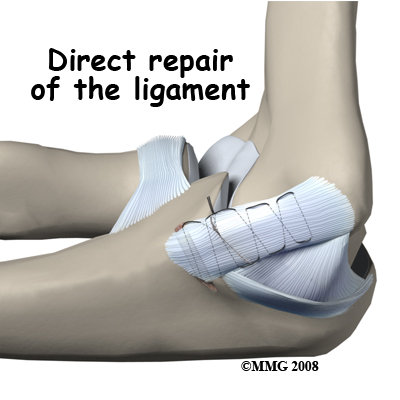

If the ulnar collateral ligament has been injured acutely due to a fall on the outstretched arm, a direct repair of the ligament may be possible. If the ligament has pulled off the bone, it may be reattached with sutures through holes drilled in the bone. If the ligament is damaged by constant overuse and is not strong enough to restore stability to the elbow joint if it is simply re-attached or repaired, then the ligament must be replaced with a new ligament. This is termed a ligament reconstruction. During a reconstruction, the ulnar collateral ligament along the medial (inside) of the elbow is replaced with a tendon graft harvested from somewhere else in the body (autograft). One common technique used to replace the damaged ulnar collateral ligament is called the technique.